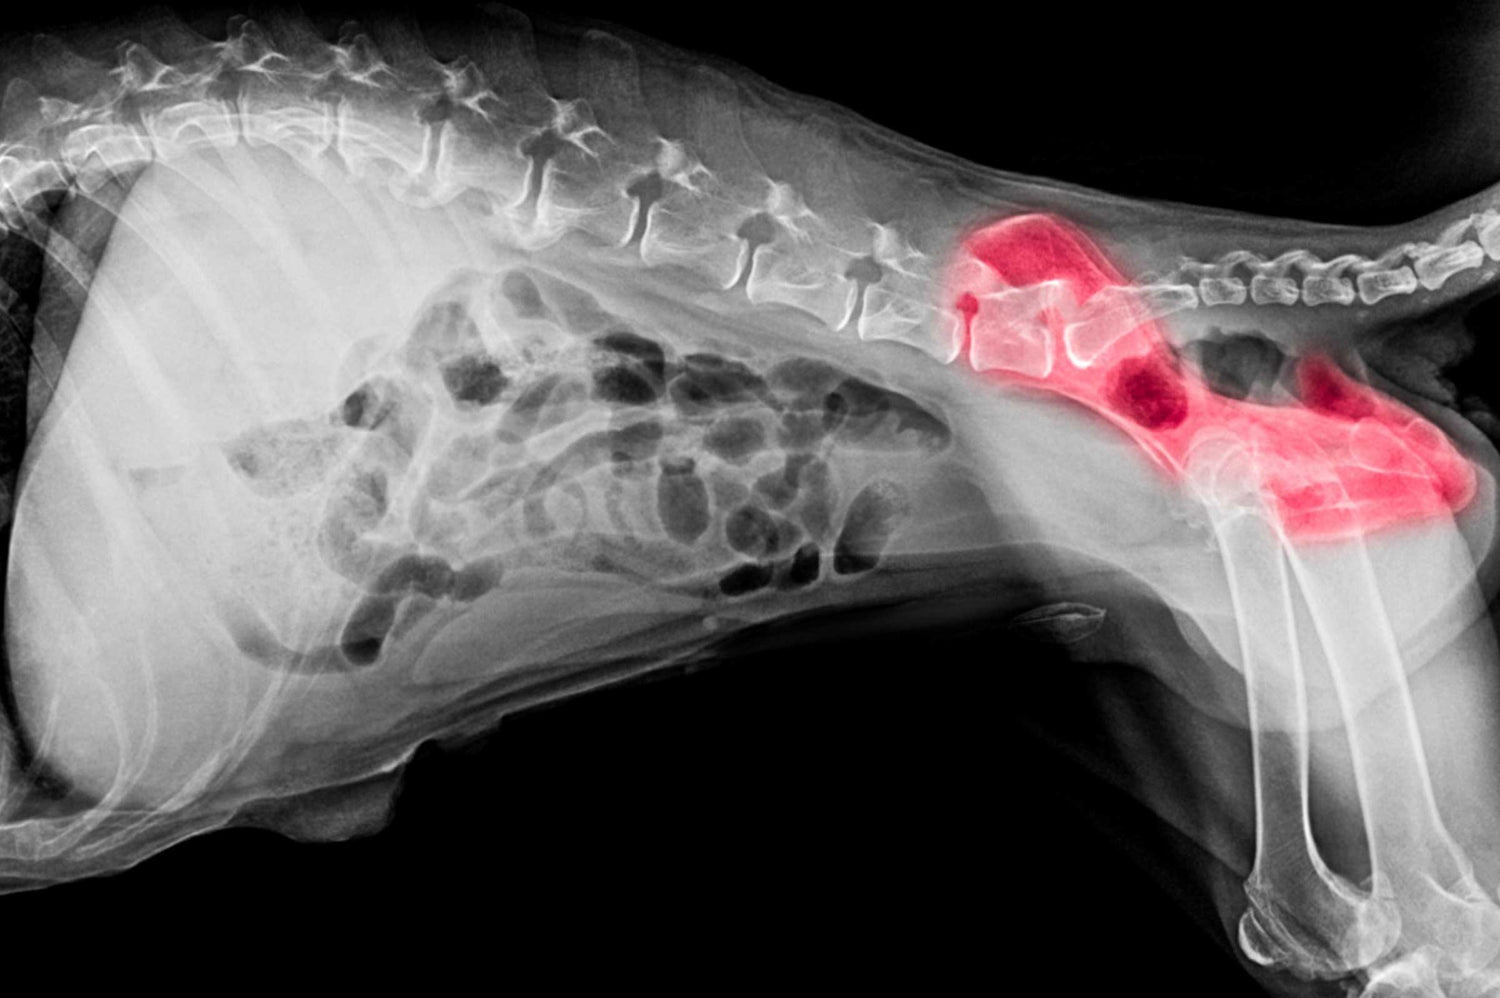

Cartilage doesn’t have its own blood supply, which makes it slow to heal. Glucosamine supports cartilage regeneration by helping produce glycosaminoglycans and proteoglycans—molecules that hold water and give cartilage its sponge-like texture. This allows joints to move smoothly and absorb impact.

By boosting the availability of these building blocks, glucosamine may slow the breakdown of cartilage and encourage repair. Over time, this can help reduce stiffness and make movement more comfortable, especially for dogs with arthritis or past joint injuries.

Joint pain isn’t just about worn cartilage. Inflammation plays a big role in making your dog feel sore or stiff. While glucosamine isn’t a direct anti-inflammatory like NSAIDs, it may help reduce the body’s inflammatory response over time.

By improving joint structure and limiting further damage, studies show glucosamine can help calm the chronic inflammation that often accompanies arthritis over time. This gentle support may allow some dogs to reduce their reliance on medications, especially when used in combination with other natural anti-inflammatories like omega-3 fatty acids or turmeric.